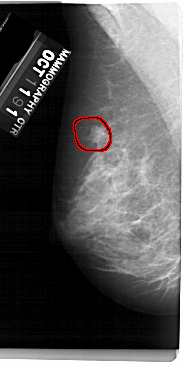

A_1432_1.RIGHT_MLO

RIGHT_MLO LINES 5491 PIXELS_PER_LINE 2851 BITS_PER_PIXEL 12 RESOLUTION 43.5 NON_OVERLAY

FILE: A_1432_1.LEFT_MLO.OVERLAY

TOTAL_ABNORMALITIES 1

ABNORMALITY 1

LESION_TYPE MASS SHAPE OVAL MARGINS OBSCURED

ASSESSMENT 4

SUBTLETY 3

PATHOLOGY BENIGN

TOTAL_OUTLINES 1

BOUNDARY